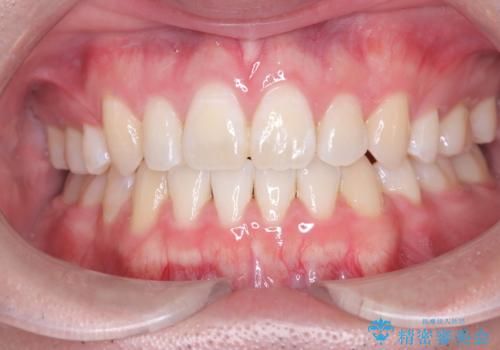

[前歯のねじれ 部分]ワイヤーとマウスピースの併用矯正治療

担当医 大元洋佑